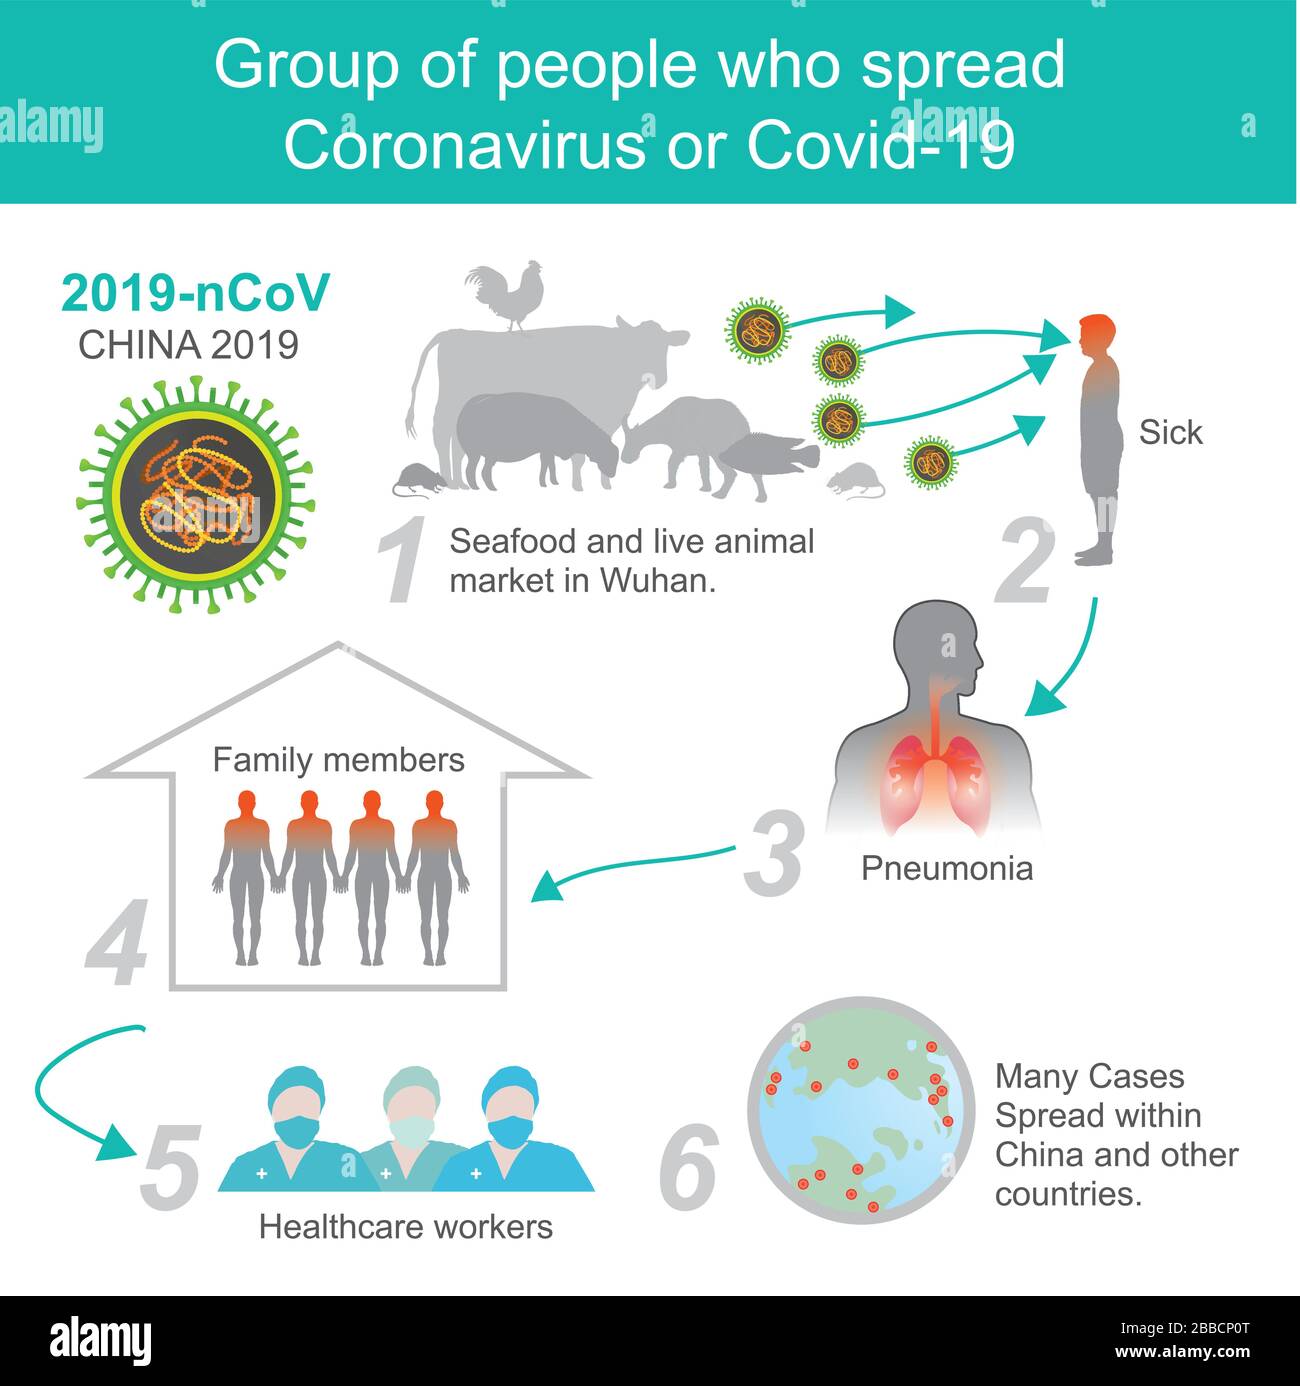

Gruppo di persone Coronavirus o Covid-19. Illustrazione sanità e medico. Illustrazione Vettorialehttps://www.alamy.it/image-license-details/?v=1https://www.alamy.it/gruppo-di-persone-coronavirus-o-covid-19-illustrazione-sanita-e-medico-image351249272.html

Gruppo di persone Coronavirus o Covid-19. Illustrazione sanità e medico. Illustrazione Vettorialehttps://www.alamy.it/image-license-details/?v=1https://www.alamy.it/gruppo-di-persone-coronavirus-o-covid-19-illustrazione-sanita-e-medico-image351249272.htmlRF2BBCP0T–Gruppo di persone Coronavirus o Covid-19. Illustrazione sanità e medico.